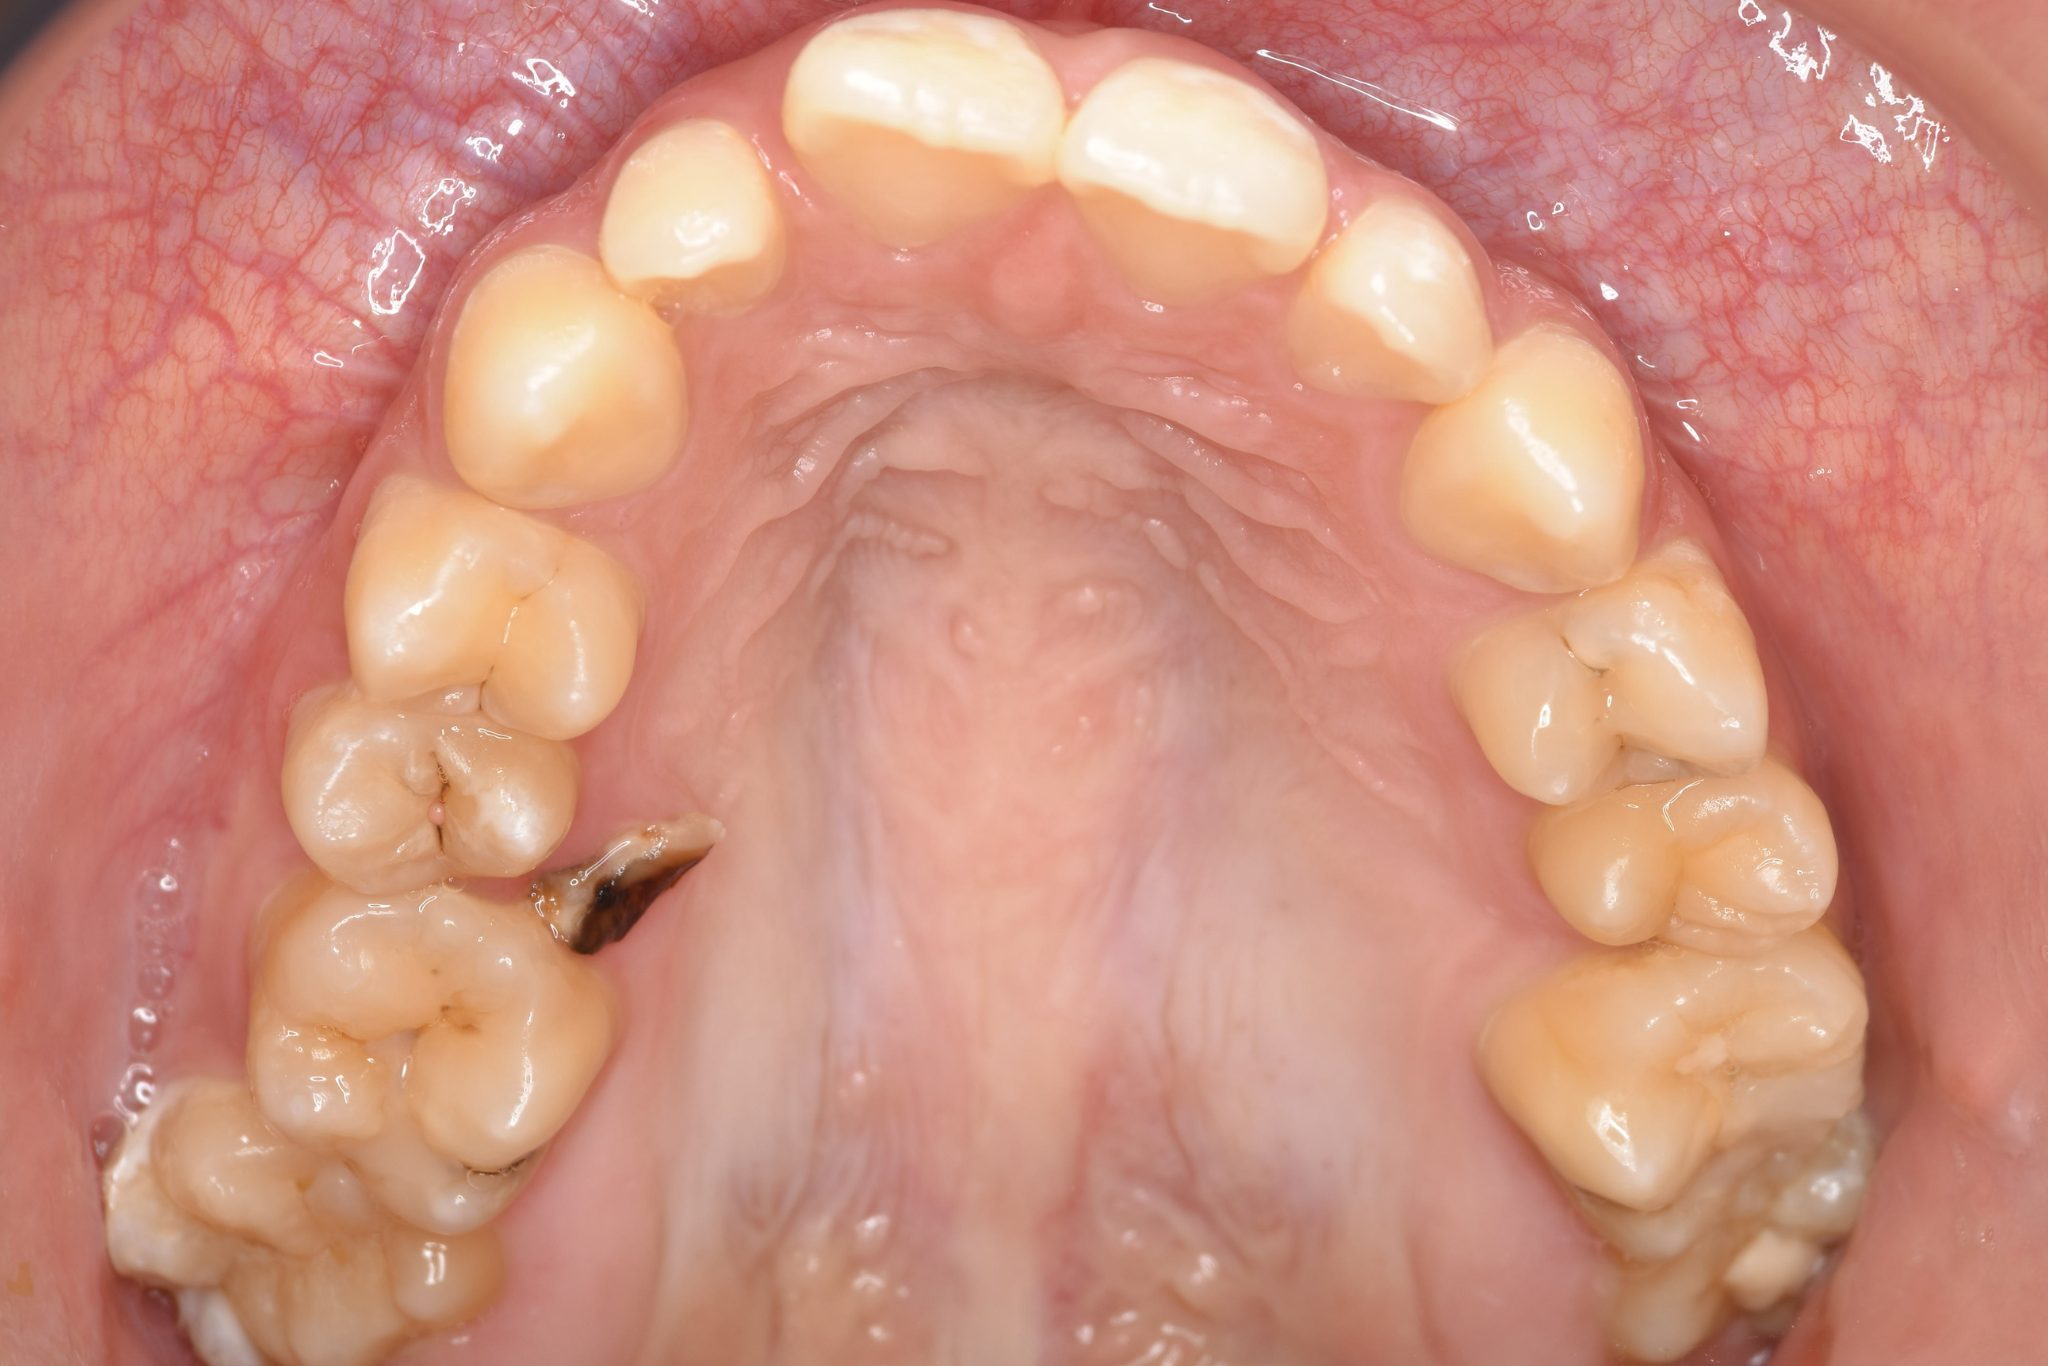

ビフォー

ワイヤー矯正治療|症例_032

主訴 歯並び|かみ合わせ

施術内容 MSEと下顎リンガルアーチを用いて上下顎骨を拡大した。

その後マルチブラケット装置を用いて非抜歯で歯牙を配列し良好な咬合を獲得した。

吸指癖と鼻閉症状は改善した。